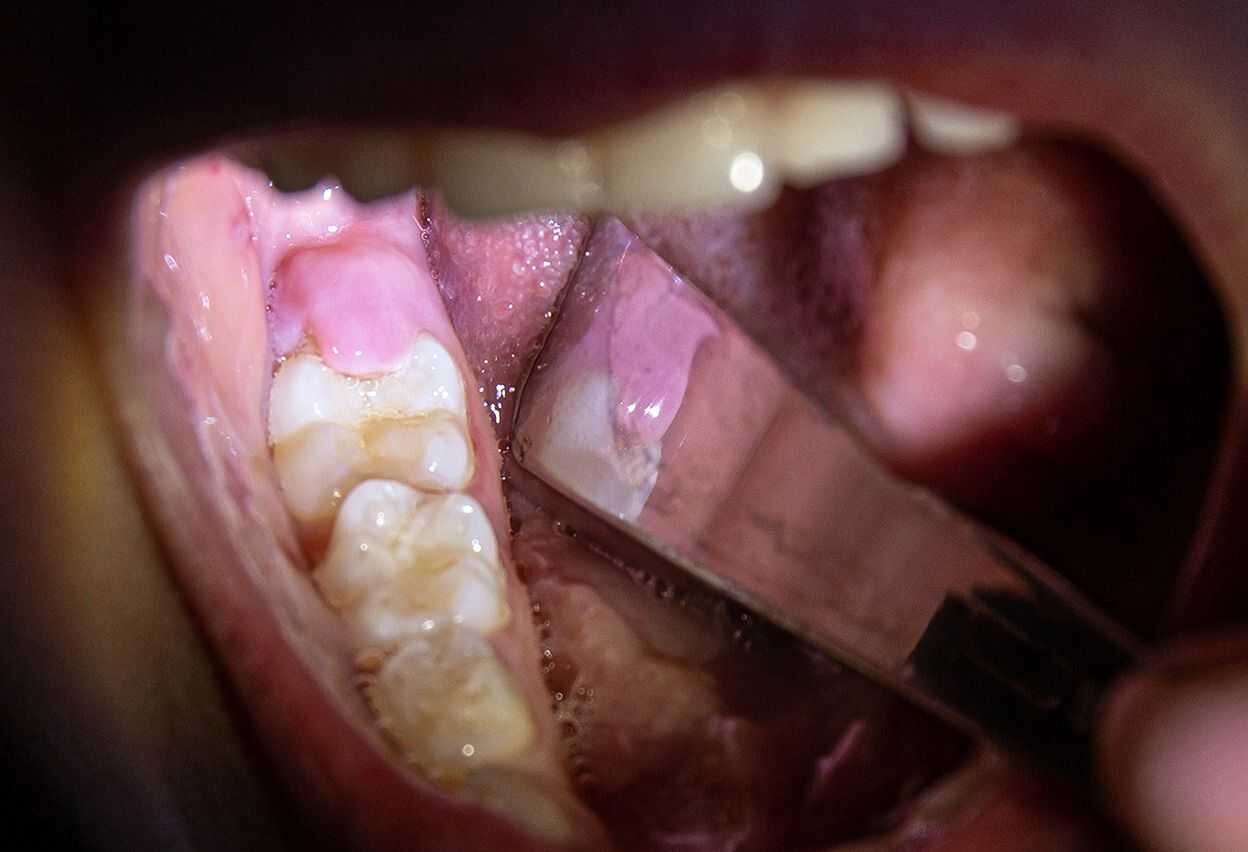

If your wisdom teeth have started to come in, you may notice that a loose flap of gum tissue has developed around them. This piece of tissue is known as an operculum, and it often develops over partially erupted teeth or teeth that do not have enough room to come in.

While some operculums only partially cover a wisdom tooth, some may cover much of the chewing surface. If the flap is large, you can have an increased risk of biting the adjacent cheek tissue or the operculum itself.You can keep your enamel and attached gingiva clean with both brushing and flossing.

Operculums, on the other hand, can be difficult to keep clean since they are in the back of the mouth and because the loose tissue may trap bacteria and food debris.